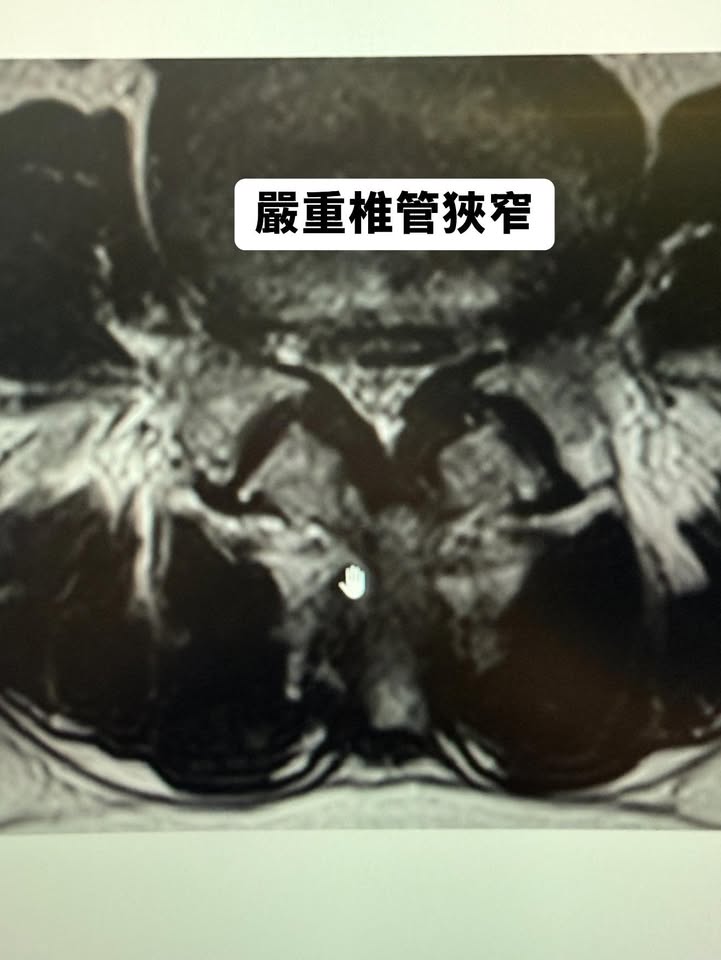

當天,我們的團隊迅速完成檢查,影像清楚地顯示出腰椎第三、第四節明顯的椎間盤突出,並合併椎管狹窄。此外,第四與第五節椎間盤也有退化和壓迫的跡象。影像一目了然,卓老太太也明白了她的問題所在。這是一場突如其來的考驗,但我告訴她:「這不一定需要手術,我們可以用其他方法幫您解決。」她的眼神中浮現出一絲希望,帶著半信半疑的表情決定接受我們的治療計畫。